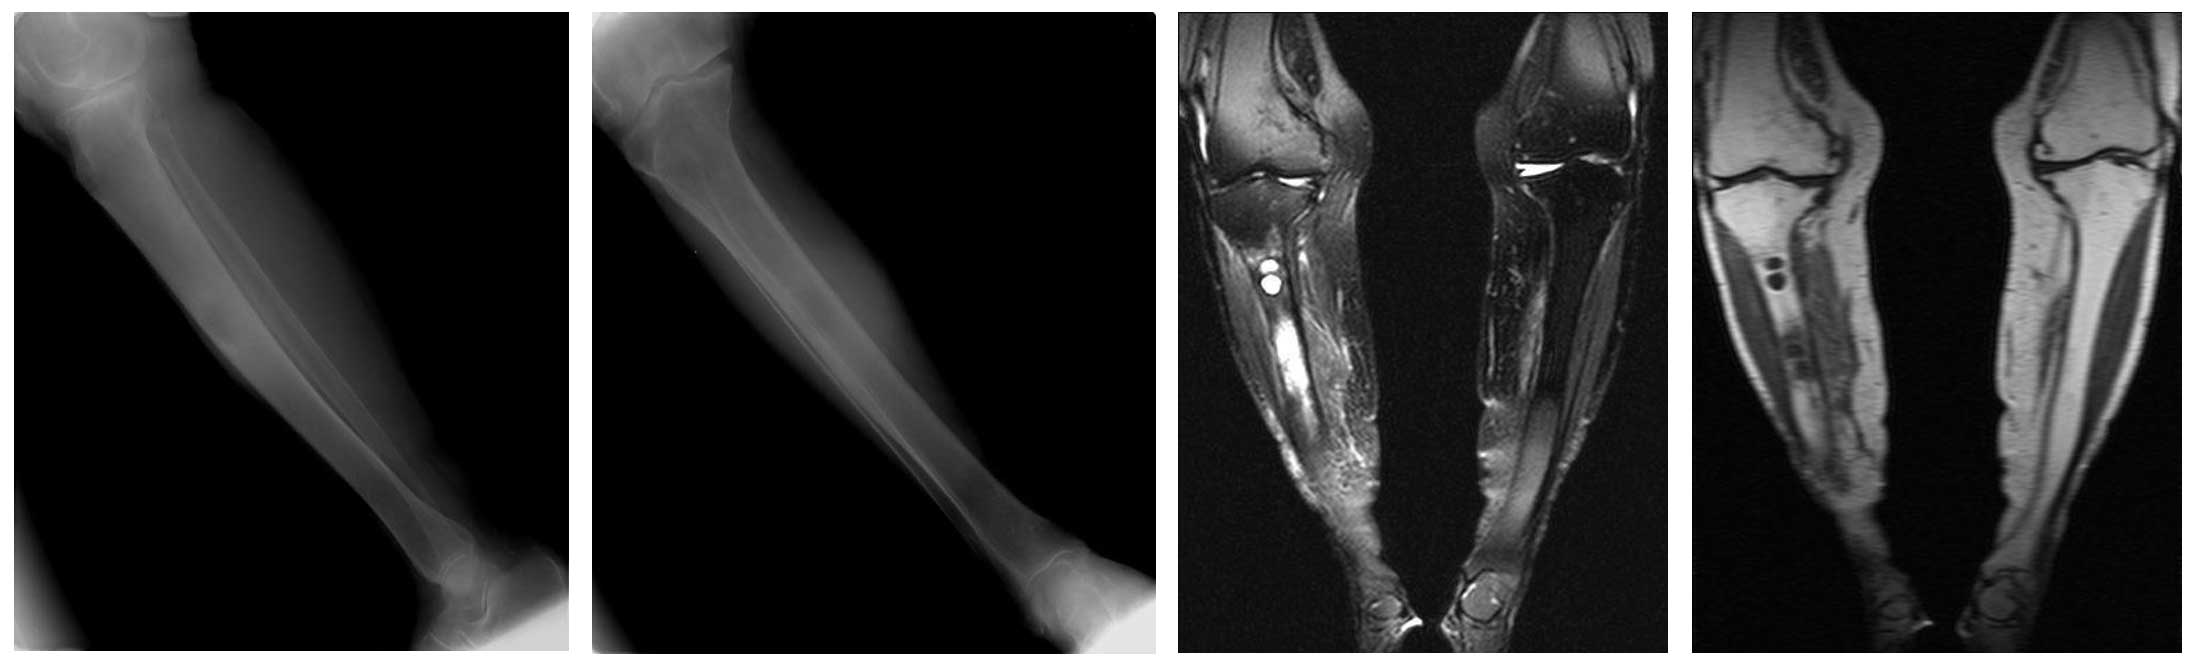

Ameliyat Öncesi: Röntgen ve MR’da sağ kaval kemiği orta bölgede metastaza bağlı harabiyet ve çevreleyen ödem görülmekte.